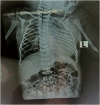

Case presentation: This report discusses a case of a male infant, two days old diagnosed with Patau syndrome. After birth, his APGAR score was satisfactory. The initial clinical examination revealed cleft palate, cleft lip, and congenital clubfoot. A pansystolic murmur was heard at the left sternal border. The patient was managed according and was referred to a surgeon for pulmonary binding, PDA ligation, VSD closure, and repair of ASA with disbanding of the pulmonary artery.

Clinical discussion: Studies have reported that patients with Patau syndrome present with cleft lip and palate, congenital heart defects, omphalocele, and holoprosencephaly. we also discovered dysmorphic characteristics such as the cleft palate and cleft lip, as well as serious congenital cardiac abnormalities. In addition, up to 80% of patients have been documented to have cardiac abnormalities, with patent ductus arteriosus, atrial septal defect, and ventricular septal defect.